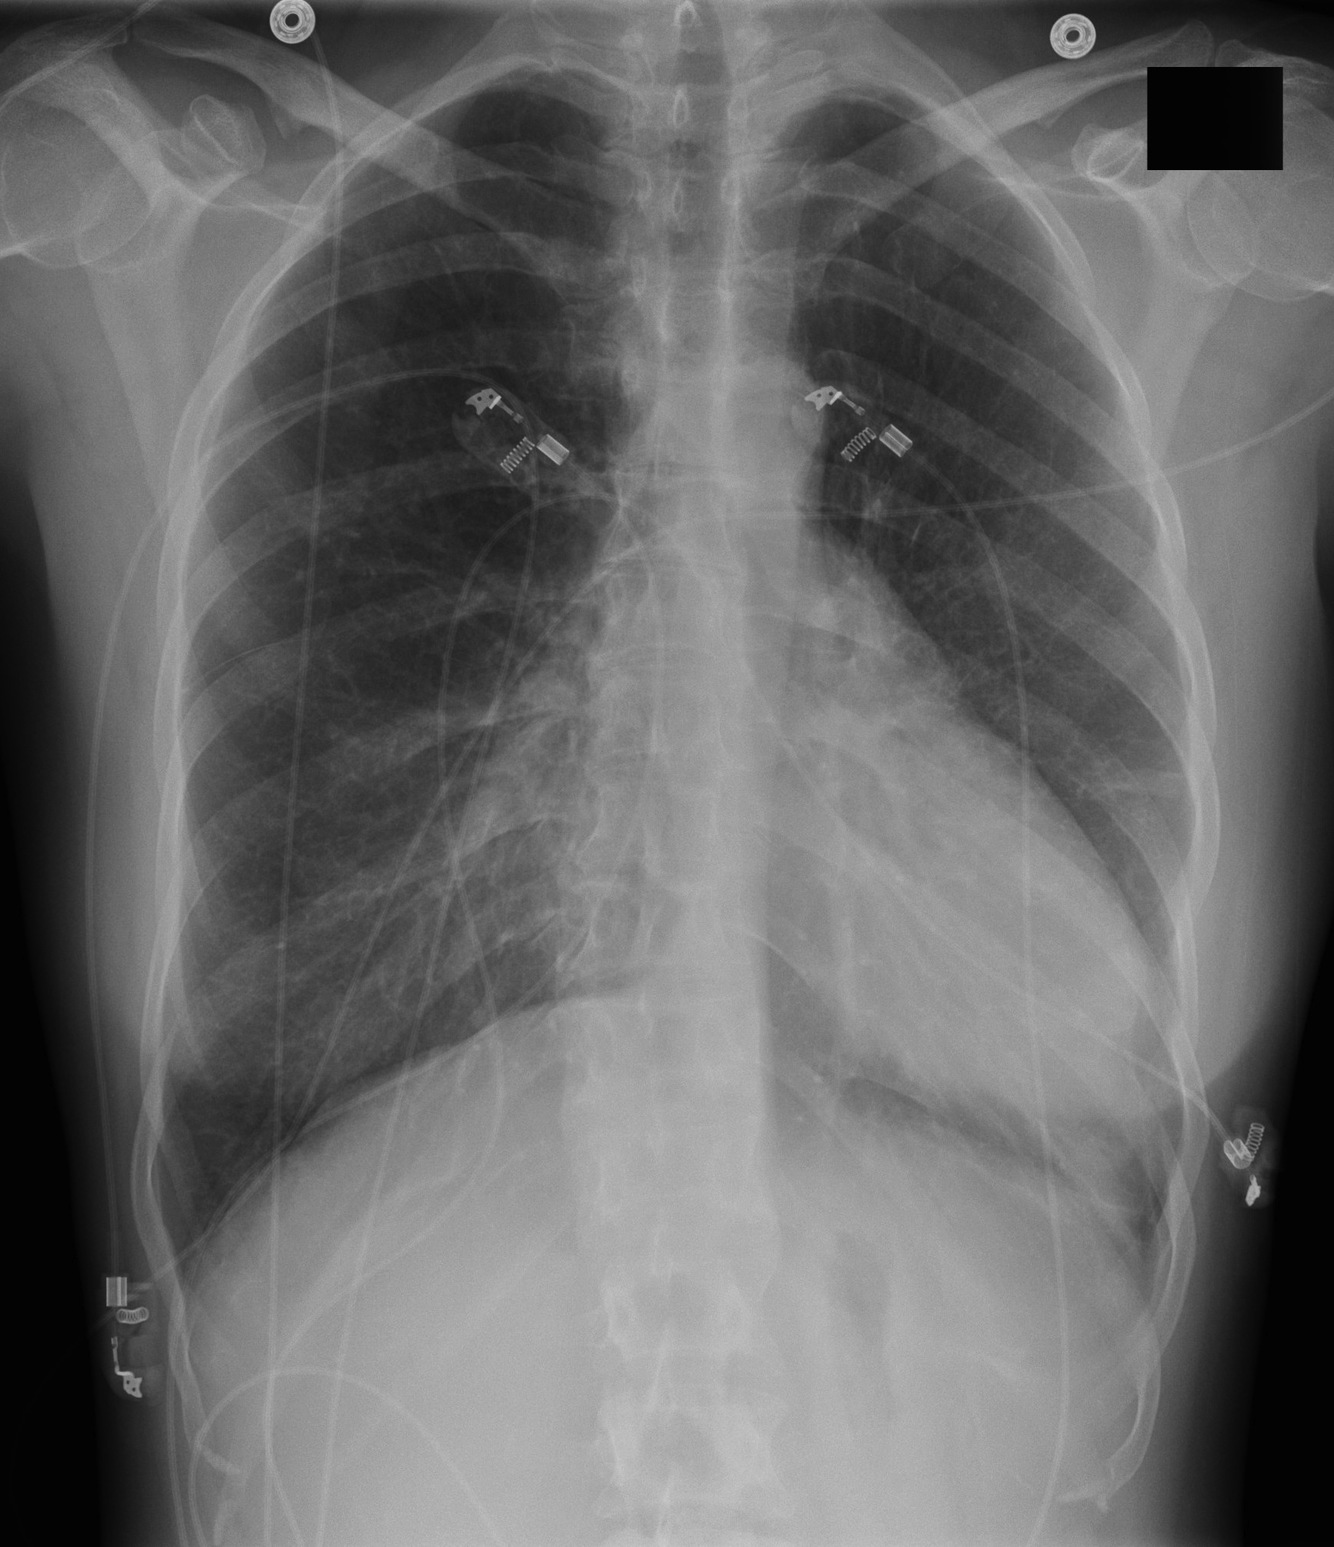

67-year-old male with history of prosthetic aortic valve stenosis, now with dyspnea on exertion and lower extremity swelling

Vertical retrosternal opaque stripes representative of possible pericardial effusion (“oreo cookie sign”).